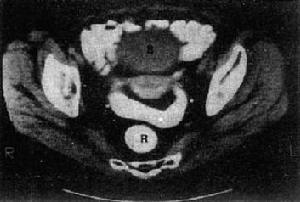

卵巢癌在初診時多數已屬晚期,CT顯示卵巢腫塊可為囊性、囊實性及實性,一般情況下,腫瘤越大,實性成份越多,則其惡性可能性越大。腹腔內種植轉移為卵巢癌最常見的轉移方式,腹腔積液有助於襯托出腹膜轉移灶,呈小結節狀、斑塊狀或餅狀,好發部位為大網膜、腸系膜、肝、脾、橫膈的表面等,CT診斷的特異性較高。CT掃描可明確卵巢癌的大小和範圍、是否侵犯鄰近結構或器官及有無遠處轉移情況,評價治療效果及了解術後復發。